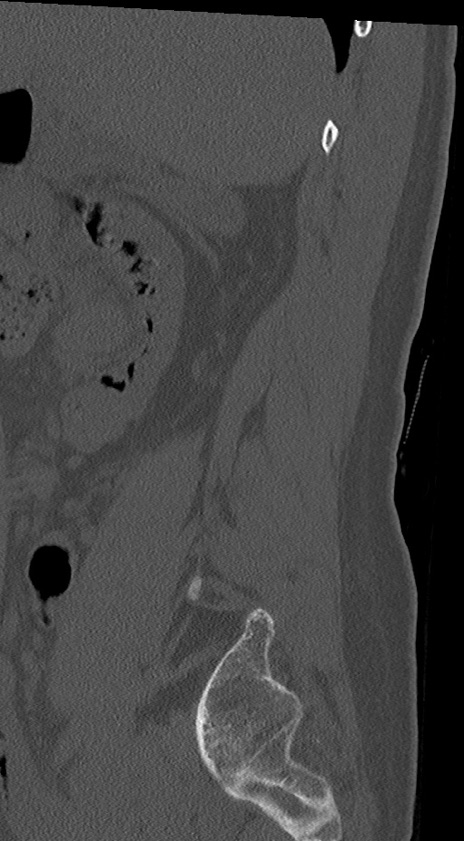

腰椎CT

冠状断像